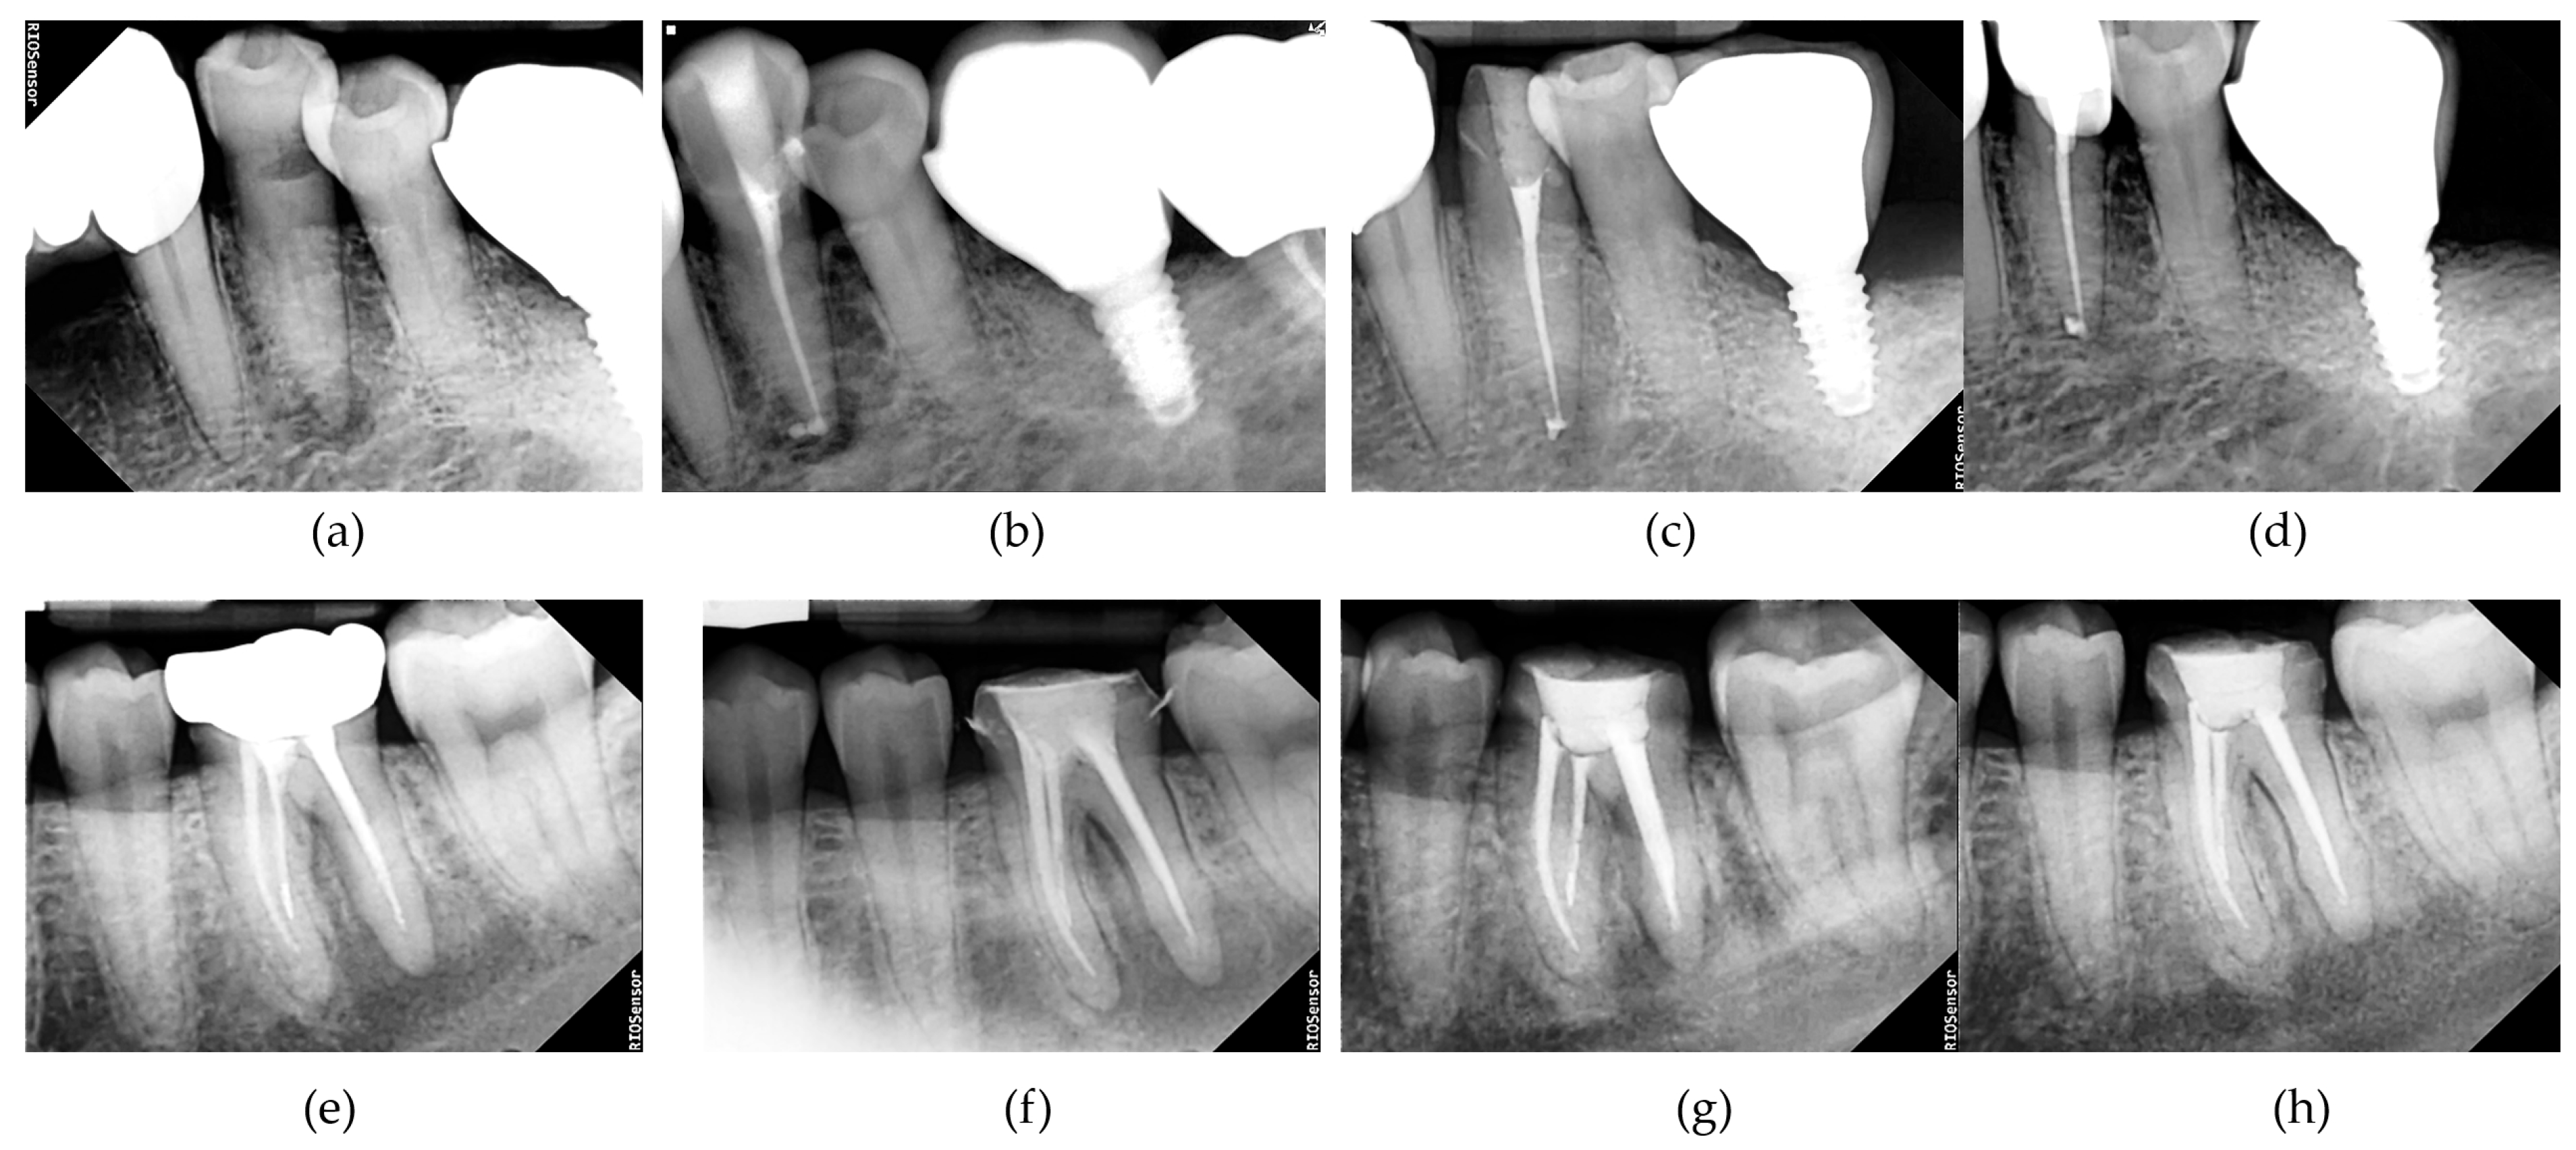

Periapical Index (PAI) scores decreased over time in both groups. The mean PAI scores at baseline and follow-up time points (immediate post-filling, 2 months, and 4 months) showed no significant differences between the groups at any time point (all p > 0.05; Table 4; Figure 2).

Figure 2. Serial periapical radiographs illustrating the progression of periapical healing in representative cases from the UDP (test) and NaOCl (control) groups. (ad) Images from a UDP-treated tooth showing: (a) preoperative periapical radiolucency, (b) immediate post-obturation status, (c) 2-month follow-up status, and (d) 4-month follow-up status with evidence of healing. (eh) Images from a NaOCl-treated tooth at similar time points. Radiographs were acquired using a standardized digital system (RIOS Sensor; Healdens, Yongin, Republic of Korea) and were used for evaluating PAI scores by blinded evaluators.